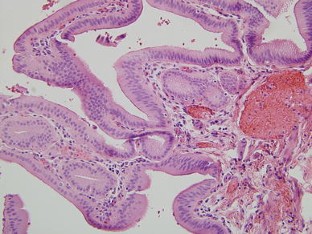

Choledochal cysts are rare, congenital malformations of the intra and/or extrahepatic biliary tree. We describe a case in which a patient was transferred to our hospital with a reported duodenal hematoma. The patient ultimately required exploration when his condition deteriorated. Laparotomy resulted in the discovery and successful treatment of a ruptured type IV-A choledochal cyst.

Fig. 3